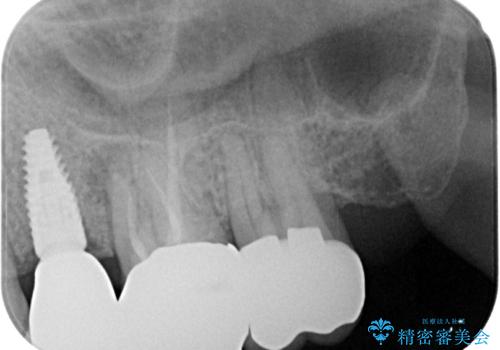

- 銀歯がとれたのでやり替えたいとのことで来院された患者様です。何度も同じ部位の銀歯の脱離を繰り返しており、メタルインレーの不適合も認めていたためオールセラミッククラウンにて補綴治療を行っていくことにしました。

拡大鏡視野下で、セラミックの被せもの、虫歯の除去を行い、オールセラミッククラウンに適した形に整えました。

歯と歯茎の間に圧排糸と言われる糸を入れてシリコーン印象材にて型どりをしました。